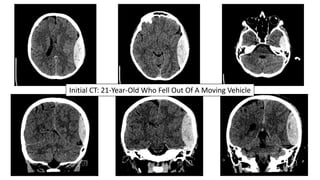

Initial CT: 21-Year-Old Who Fell Out Of A Moving Vehicle

Case #1

21-year-old female brought into the ED after she fell out of an open-door

Jeep traveling at approximately 10 miles per hour.

Clinical Course:

• Intubated with immediate pre-intubation GCS of 13

• Transferred to our Trauma Center with the neurosurgical team awaiting

• Underwent emergent left craniotomy

• Extubated one day after surgery and found to be neurologically intact

• Discharged home on Post-Operative Day #2

21-Year-Old Who Fell Out Of A Moving Vehicle

Left Temporal EDH CT On Post-Operative Day #2